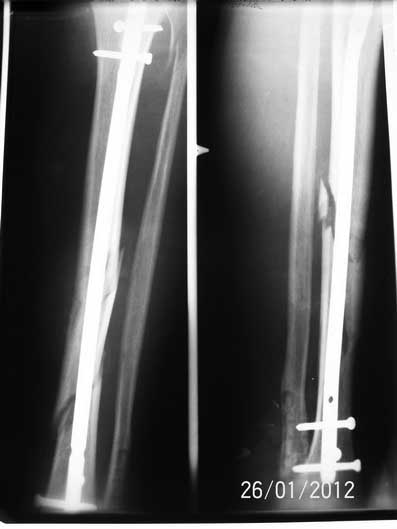

Спасибо всем откликнувшимся! Докладываю результат. Свищ после удаления лигатуры за неделю затянулся. Фиксаторы с лодыжек удалены, БИОС. Мы удовлетворены, пациент доволен.

1. Снимок датирован 260112 (как исходный так и послеоперационный)

Ув. Андрей! Это не было желанием похвалиться. Это было желание услышать мнение незаинтерисованных коллег. Просто нам было настойчиво рекомендовано оперировать открыто пластиной. Хотелось узнать найдет ли кто в данной ситуации преимущества использования пластины перед БИОС, мы таки не нашли - и вот результат.